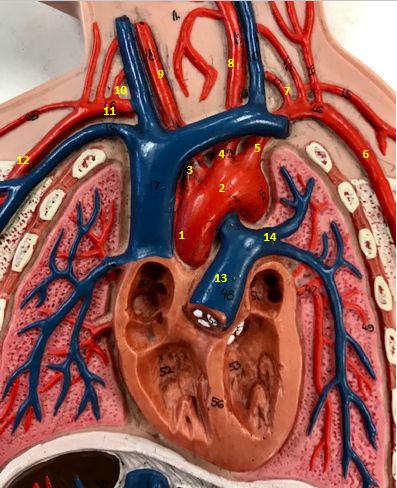

Aorta

Name #2

Brings blood out of left ventricle

Function of aorta

Brachiocephalic artery

Name #3

Supplies oxygenated blood to right arm shoulder neck and head

Function of brachiocephalic artery

Left common carotid artery

Name #4

Supplies oxygenated blood to left neck and head

Function of left common carotid artery

Left subclavian artery

Name #5

Supplies oxygenated blood to left arm shoulder

Function of left subclavian artery

Left axillery artery

Name #6

supplies blood to left armpit and upper limb

Function left axillary artery (6)

Left vertebral artery

Name #7

Supplies blood to brain and spinal cord

Function of left vertebral artery (7)

Left common carotid artery

Name #8

Supplies blood to left neck and head

Function of left common carotid artery (8)

Right common carotid artery

Name #9

Supplies oxygenated blood to right neck and head

Function of right common carotid artery (9)

Right vertebral artery

Name #10

Supplies blood to brain and spinal cord

Function of right vertebral artery (10)

Right subclavian artery

Name #11

Supplies blood to right arm and shoulder

Function of right subclavian artery

Right axillery artery

Name #12

Supplies blood to right armpit and upper limb

Function of right axillery artery (12)

Pulmonary trunk

Name #13

Bring blood out of right ventricle to lungs

Function of pulmonary trunk (13)

Left pulmonary artery

Name #14

Bring blood to left lung

Function of left pulmonary artery (14)